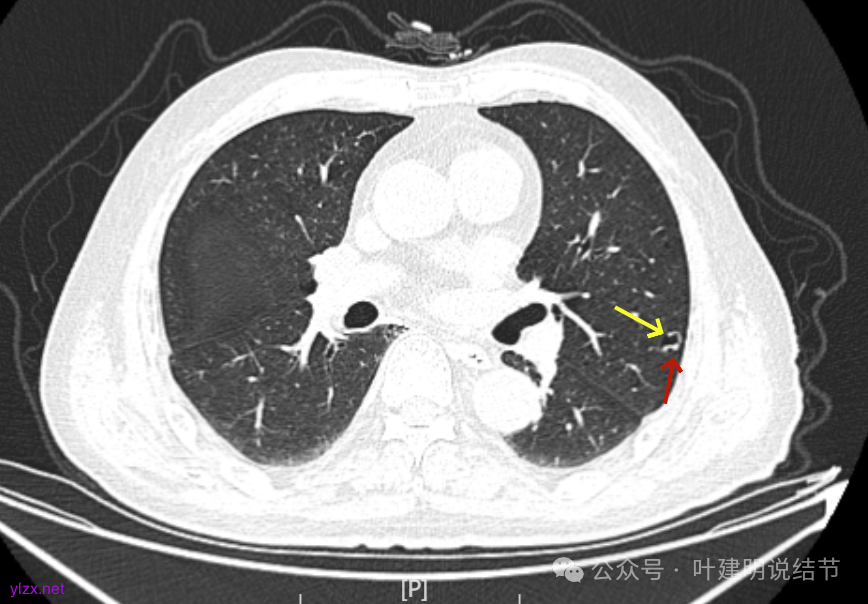

先来看2025年1月的影像:

病灶出现,有少许磨玻璃成分,整体轮廓较清,实性部分较为光滑。

有囊腔,表面不平,部分囊壁是磨玻璃成分。

病灶囊壁稍不均,多密度较高,表面欠平。

病灶整体的囊壁稍不均,靠内侧有磨玻璃成分。

囊壁不厚但密度较高。

囊腔内壁稍显不光滑,有少许突起于囊腔内。

上图也见囊腔内壁有突起,此层囊壁大部分呈磨玻璃密度。

边缘区是淡磨,内壁少许突起。

冠状位见病灶囊壁不均,表面不光滑,囊腔内壁也不太平整。

矢状位见病灶囊壁有结节状高密度。

右下叶也有囊腔灶。

两肺其他地方多处肺大泡。

左肺上叶红色这处是囊腔型病灶,囊壁略不均,似有微小血管进入囊壁,对比2023年4月整个囊腔来讲有扩大,需要考虑囊腔型肺癌的可能性大。右侧蓝色的并不是典型囊腔型肺癌的表现,再加上两肺绿色这些慢支肺气肿与肺大泡的影像,右侧的就更加不确切,至少近期不能够考虑右侧也要开刀的事情。其实左侧的主病灶相对于其他表现更典型的囊腔型肺癌来说,由于囊壁密度偏高,也不是百分百必定是肺癌。我的想法还是先等脑梗情况稳定,并且间隔4~6个月复查病灶再有进展在考虑单孔胸腔镜下局部切除就可以。淋巴结可以考虑采样,但一般不至于阳性。破是不会切破的。消融不建议,囊腔灶更难通过穿刺获得病理依据,况且东西在边上,能局部楔切,当然首选手术。意见供参考!